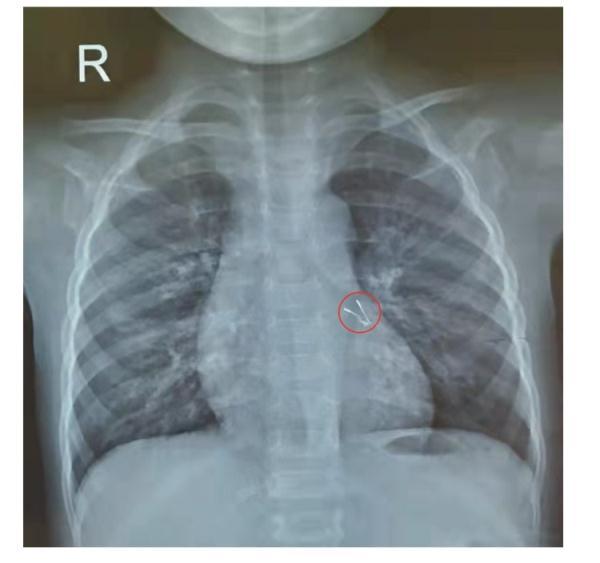

1、孩子突然咳得很严重,并有呼吸困难时,可能有异物堵住了气管,如果能够立刻发现,采取急救措施取出来还好,如果一直没有发现有异物卡在气道就十分危险了。